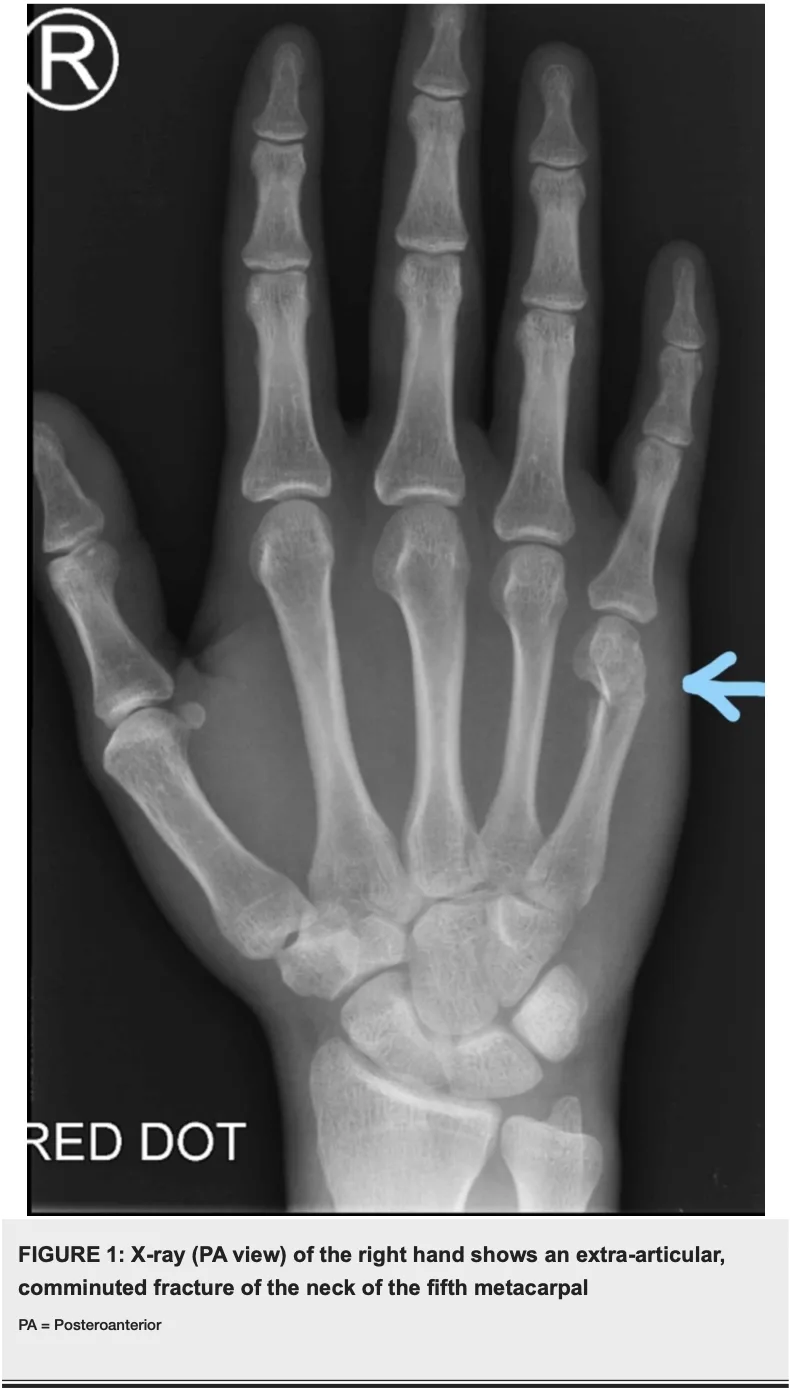

第5中手骨頚部骨折の患者

続いて, 昨日転倒し手の痛みを訴える後期高齢患者さんを診察.

小指の付け根に圧痛があり, X線で第5中手骨頚部骨折を確認しました.

拳を強く打ちつけることで起こりやすく, ボクサー骨折として知られる骨折です.

X線透視下でできる限り真っ直ぐに戻して副子固定を行いました.